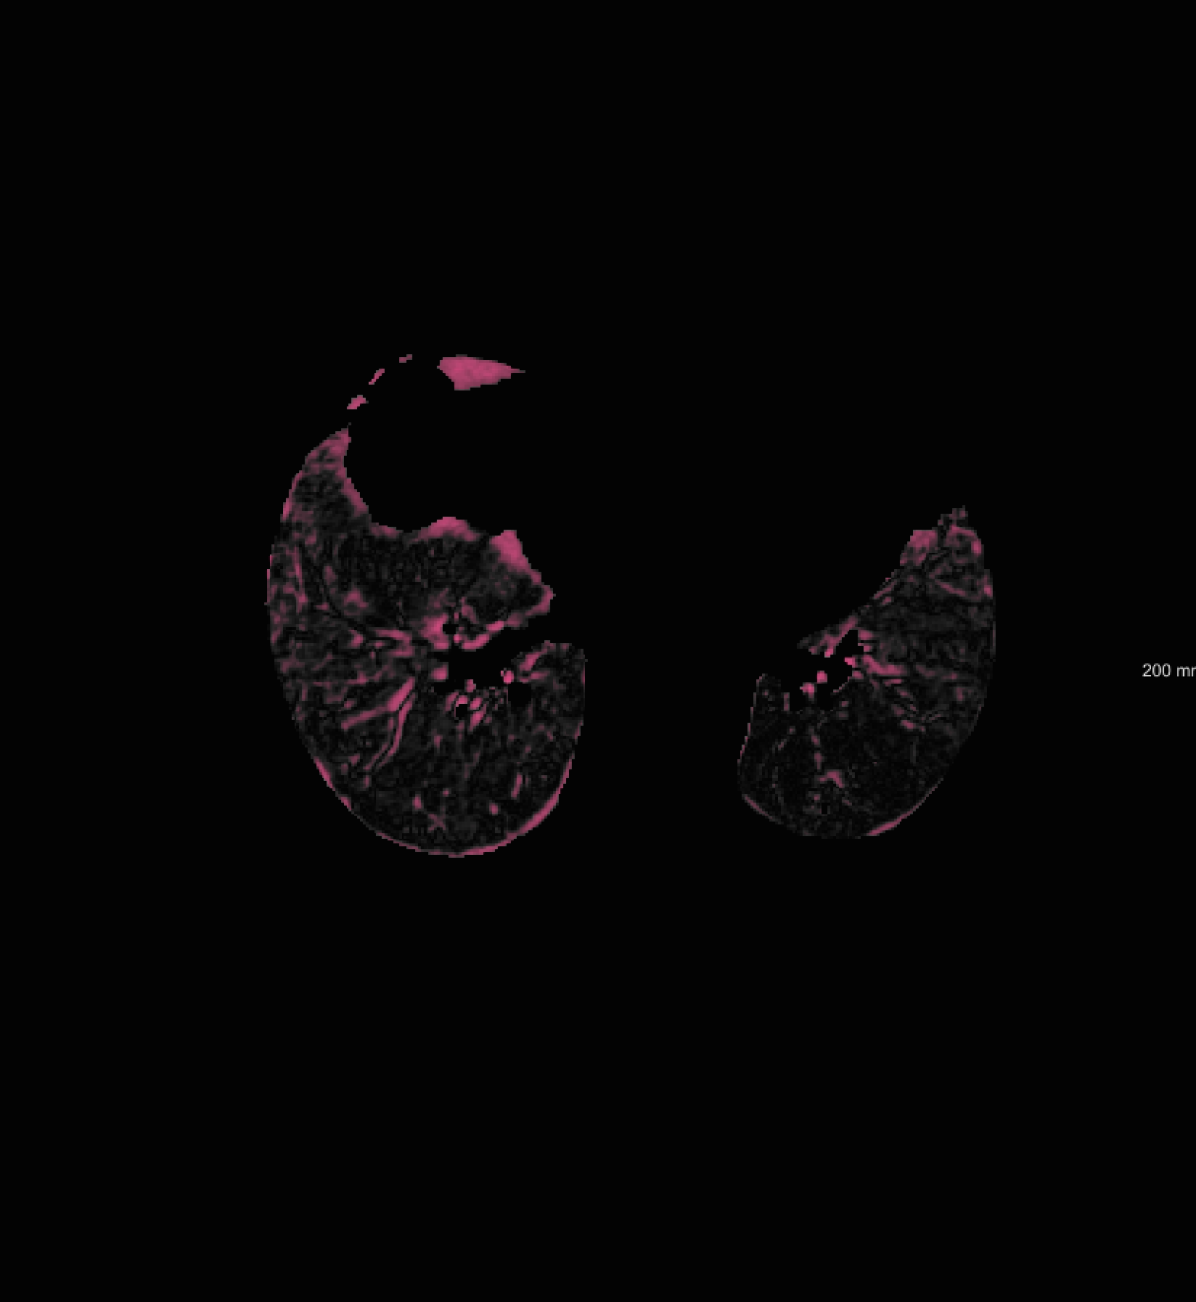

respiratory motion: We simulate respiratory motion with three components similar to Hub et al. (2009) as follows: Expansion of the chest in the transversal plane with a maximum scaling factor of 1.12; Transition of the diaphragm in cranio-caudal direction with a maximum deformation of ; Random deformation using the single frequency method. In order to locate the diaphragm, an automatically detected lung mask is used.

For the DIR-Lab-4DCT database, a comparison between RegNet and affine, B-spline (three resolutions), an advanced conventional registration method using sliding motion (Berendsen et al., 2014) and three other CNN-based methods (Eppenhof and Pluim, 2018; de Vos et al., 2019; Sentker et al., 2018) is available in Table IV. It can be seen that training with “S+M” improved performance slightly with respect to just “S”. Adding the respiratory motion category improved performance substantially, as these are inhale-exhale pairs; this is predominantly caused by the patients where the TRE after affine registration was still quite large. An example visualization is also available in Fig. 5(f), showing that adding the respiratory motion category can align images better in the diaphragm region. The advanced conventional registration method that leverages sliding motion (Berendsen et al., 2014) is still better than RegNet. Note that RegNet was not trained on the DIR-Lab-4DCT data, similar to Eppenhof and Pluim (2018); Sentker et al. (2018). However, de Vos et al. (2019) and Eppenhof and Pluim (2018)-DIR methods were trained on the same database but using cross-validation to report the results. Also note that the results reported in Sentker et al. (2018) are averaged over all phases of DIR-Lab-4DCT (T00 to T10), while the results of other CNN methods (including RegNet) are reported between the maximum inhale and maximum exhale phase (T00 and T50). These reported results are therefore likely somewhat better than the results for T00 and T50 only.